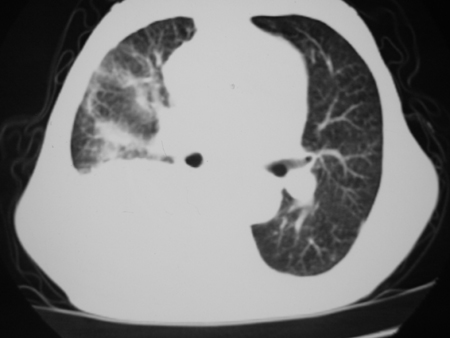

标题: CT24778:肺部病变

男77岁,胸痛就诊

右侧胸腔积液,部分包裹,右下肺膨胀不全,右下肺感染。

考虑右肺门占位并下叶不张 右胸包裹积液

右肺中叶及下叶炎症并胸腔积液(部分包裹),建议抽液后复查ct除外占位。